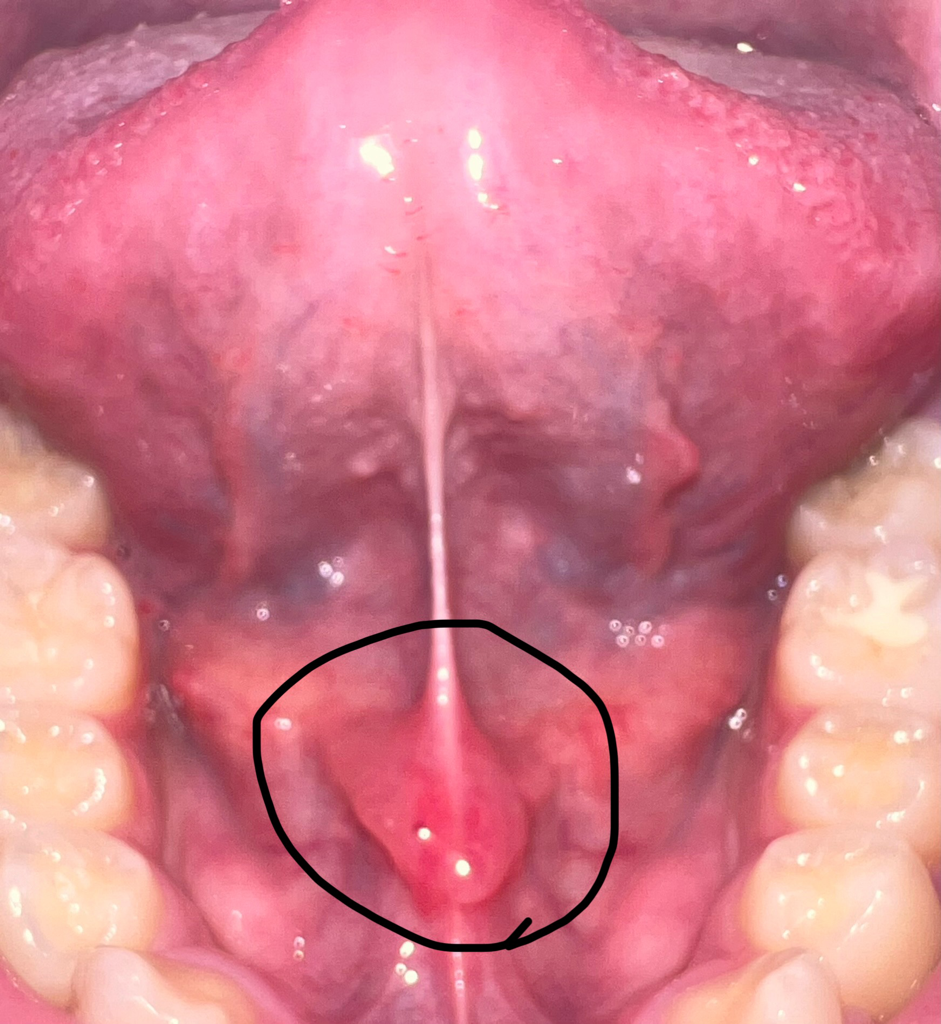

감기 걸린 후 혀밑이 아파서 보니깐 다른 날보다 많이 부어있는데 많이 심각한가요?

기다리면 좋아지나요? 바로 병원을 가야 할까요?

• 1번 째 사진

정상적인 것입니다. 그냥두면 됩니다. 동그라미 친 부위는 침이 나오는 구멍입니다. 혀가 불편한 것은 시간이 지나면 좋아집니다.

설소대가 부으신거 같은데 크게 문제는 아닙니다. 시간이 지나면 괜찮아 지실꺼에요. 걱정하지 않으셔도 될것같습니다.

우리 몸의 면역체계와 관련하여 림프라는 구조가 있습니다. 세균 침투로 인해 림프선이 부을 수 있는데 감기가 원인일 수도 있고 그 밖의 호흡기 감염 질환이 원인일 수도 있습니다. 혀 밑에는 림프 외에도 작은 침샘이 다수 분포해 있는데 침샘염의 가능성도 있습니다. 정확한 건 치과에 가서 진단을 받아보시기 바랍니다.

해당부위는 침샘이 있는 부위로 부어있는 것처럼 보이고 있습니다.

타액선 염이 있는 경우에 해당 부위가 붓는 경우가 있기 때문에 진료가 필요할 수 있습니다.